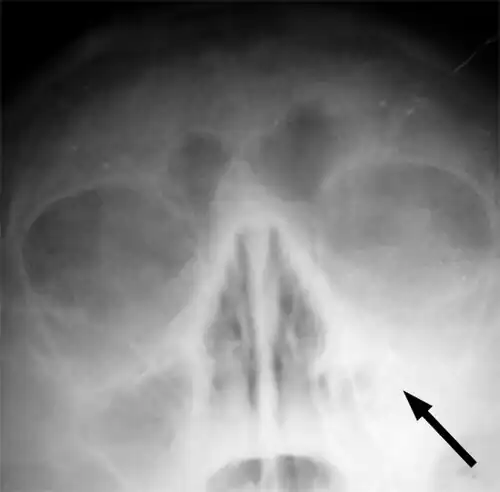

-

CT of chronic sinusitis -

CT scan of chronic sinusitis, showing a filled right maxillary sinus with sclerotic thickened bone -

X-ray of left-sided maxillary sinusitis marked by an arrow. There is a lack of air transparency, indicating fluid in contrast to the other side.